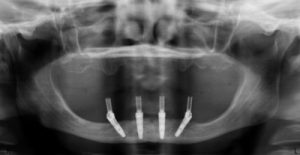

Davanti al computer quindi si pianifica l’intervento posizionando virtualmente gli impianti all’interno della compagine ossea del paziente; sarà poi una dima chirurgica individuale a guidare l’operatore nel corretto posizionamento degli impianti in bocca al paziente.

Nell’immagine qui sopra si può osservare una dima chirurgica. Questo strumento consente di inserire gli impianti nella posizione ideale con un approccio mini-invasivo, riducendo drasticamente il trauma chirurgico e i tempi operatori.